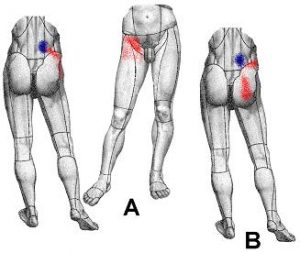

*B = dolore secondario

- *A = dolore primario in sede lombare paraspinale, approssi- mativamente sopra le faccette articolari lombari e dolore riferito all’inguine e alla parte prossimale della coscia;

- *B = dolore riferito alla natica e/o alla cresta iliaca (più raro)